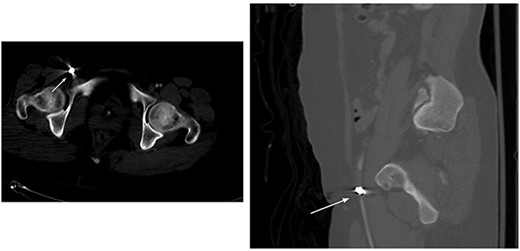

Abdomen and pelvis CT showed an intra-abdominal bullet fragment abutting the anterior gastric wall without gastric injury and a minor splenic laceration. Also, a bullet fragment in the right distal external iliac artery at the level of bifurcation (Fig. 5) causing a filling defect, however no extravasation, and the contrast passed to the superficial femoral arteries (Fig. 6).

Filling defect in the external iliac artery with no extravasation and the contrast passing to the superficial femoral arteries.